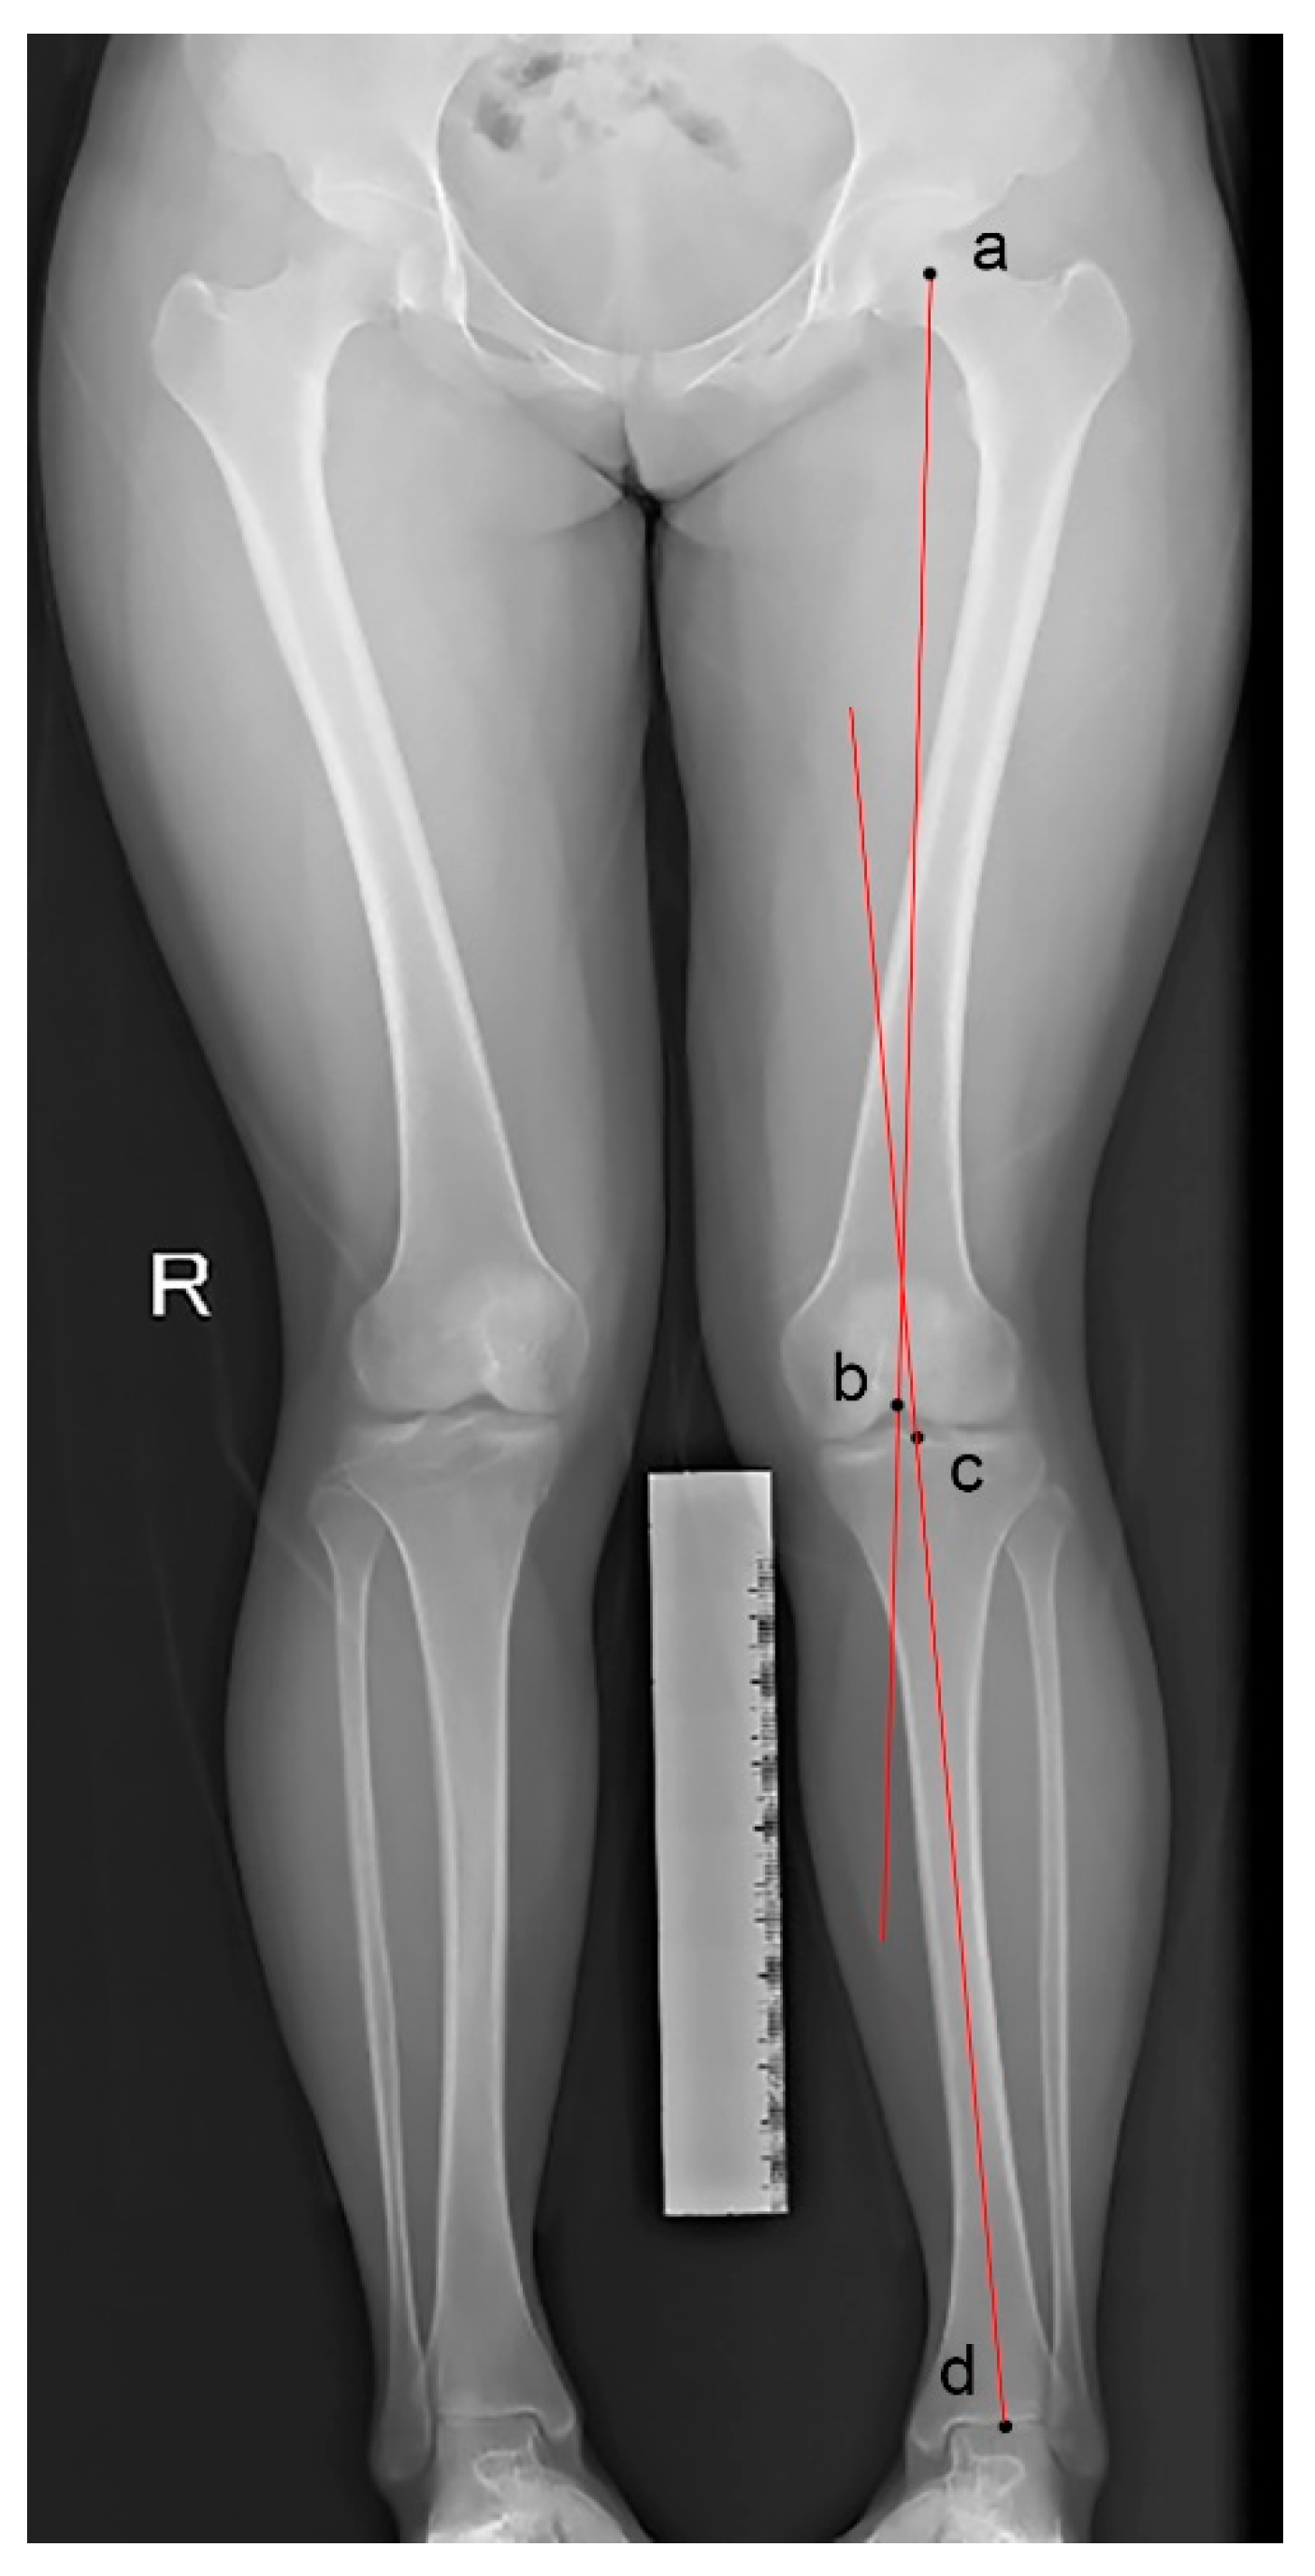

Coronal malalignment was assessed by hip–knee–ankle (HKA) angle on weight-bearing full-leg radiographs. It is defined as the angle between the femoral mechanical axis and the tibial mechanical axis [19] (Figure 4). Valgus deformity was diagnosed with a value of the HKA angle >1.5°.

Figure 4.

Hip–knee–ankle (HKA) angle measured by a weight-bearing full-leg radiograph. The points represent the center of the femoral head (a), the femoral condyles (b), the tibial plateau (c), and the ankle joint (d). It is the angle formed between the femoral axis (ab) and the tibial axis (cd).